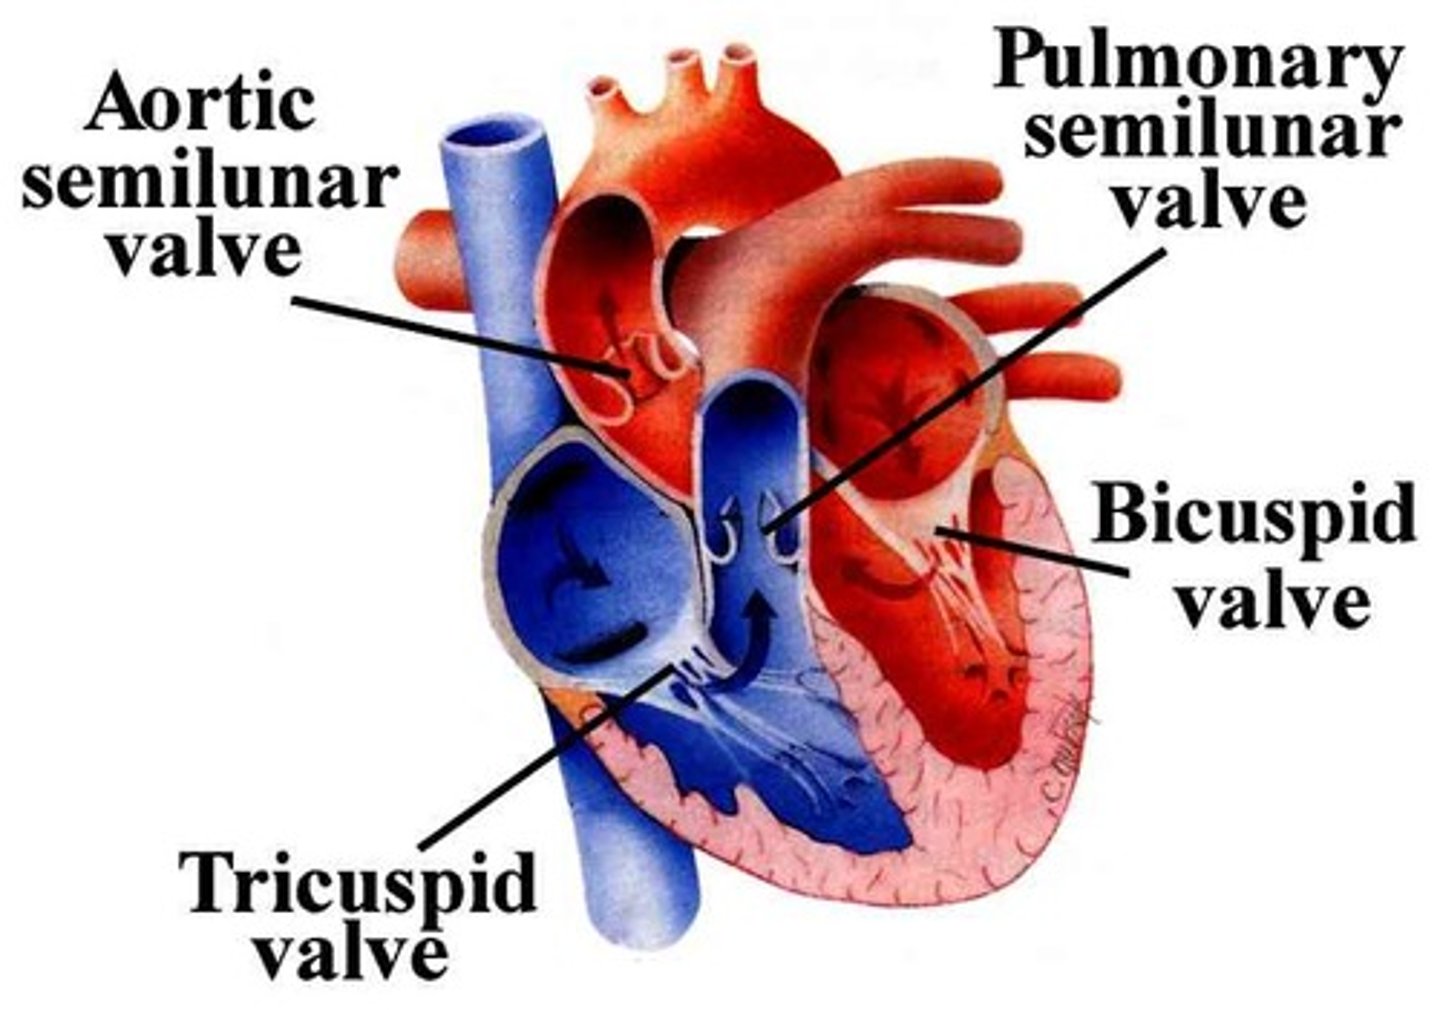

Atrioventricular valves (tricuspid and bicuspid)

Prevents back flow into atria

Semilunar valves (aortic and pulmonary)

Prevents back flow into ventricles

Both have three flaps

Don't have papillary muscles

False, the changes in pressure open and close the AV valves

True or False: The contraction and relaxation of the papillary muscles open and close the AV valves

True

True or False: The ventricles and papillary muscles contract concurrently

Lub

The first heart sound

Closing of the AV valves (tricuspid and bicuspid)

Signifies the beginning of ventricular systole (contraction)

Dub

The second heart sound

Closing of the semilunar valves

Signifies the beginning of ventricular diastole (relaxation)